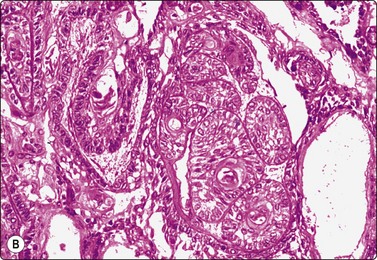

image image

Fig. 4.9 Nasopharyngeal carcinoma (undifferentiated, lymphoepithelial type, WHO type III)

Loose clusters of undifferentiated epithelial cells with vesicular nuclei, prominent nucleoli and pale fragile cytoplasm. Background of lymphocytes. (A, MGG, HP; B, H&E, HP).

Criteria for diagnosis (undifferentiated carcinoma nasopharyngeal type (UCNT)/WHO type III/lymphoepithelial carcinoma)

Undifferentiated malignant cells, single and in clusters,

Variable amount of pale, fragile cytoplasm,

Large vesicular nuclei with prominent central nucleoli,

Admixture with, and background of, lymphoid cells, often with prominent plasma cells,

Ancillary tests: neoplastic cells positive for cytokeratin, negative for lymphocyte markers. EBV-associated nuclear antigen.

Nasopharyngeal carcinoma (NPC) is a clinicopathologic entity different from other squamous cell carcinomata of the head and neck. It is distinguished by its particular histology, geographic distribution, relationship to Epstein-Barr virus, and the absence of an alcohol or tobacco etiological relationship. A proportion of NPCs show squamous differentiation and the cytological pattern of non-keratinizing squamous cell carcinoma (squamous cell carcinoma/WHO type II) (Fig. 4.8). Keratinized cells (WHO type I) are uncommonly found. The majority of NPC are poorly differentiated or undifferentiated. Cells from undifferentiated NPC (UCNT, WHO type III) form loose clusters with no specific microarchitectural pattern, and are usually mixed with lymphoid cells. In the ‘lymphoepitheliomatous’ type (Schmincke-Regaud) the cells tend to be less cohesive, resembling Hodgkin’s disease or large cell non-Hodgkin lymphoma. However, in NPC, the malignant cells are still clustered and have more abundant pale cytoplasm contrasting with the lymphoid cells in the background (Fig. 4.9). Plasma cells are frequently found among the lymphoid cells. Immunostaining for cytokeratin and a pan-lymphocyte marker is helpful. Epstein-Barr virus-associated nuclear antigen is demonstrable by anticomplement immunofluorescence in undifferentiated tumors. Other patterns of growth may occur and may cause diagnostic problems; for example, spindle cell forms may be difficult to recognize as carcinoma.

NPC frequently presents to the cytologist as a lymph node metastasis in the neck without a known primary. Cytological recognition is important since the primary is often clinically occult.